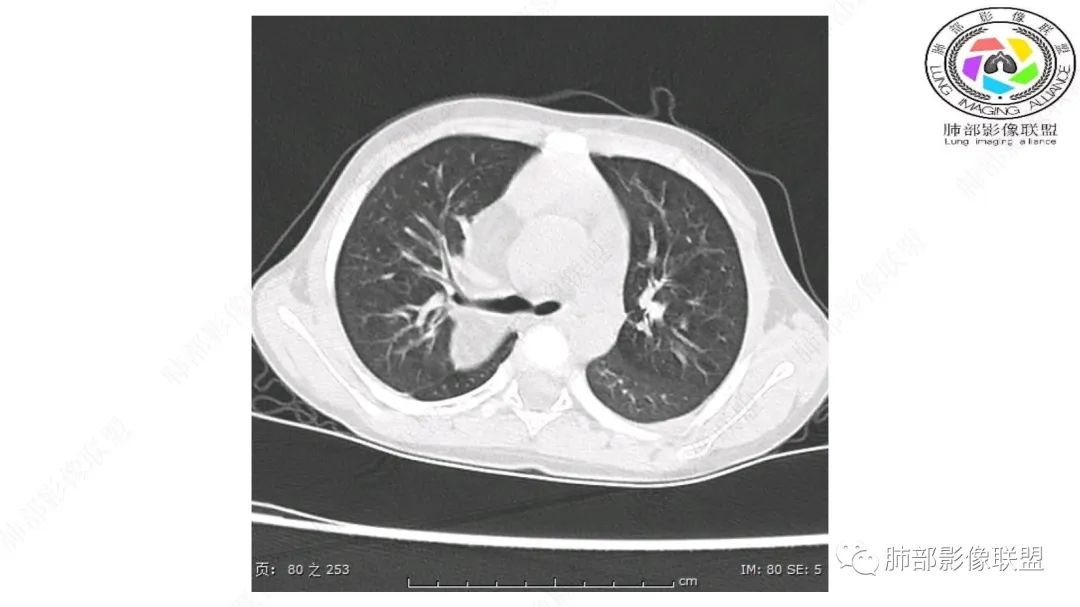

患儿3岁 咳嗽检查发现纵隔占位。右肺上叶受压表现,占位以脂肪组织密度为主,似见分隔,首先考虑为脂肪母细胞瘤,鉴别脂肪瘤,畸胎瘤。

定位:肺内?尖段气管未见明显显示,腔静脉受压向右推移?病灶内可见前段动脉穿行,脂肪密度为主。

肿块起源于右上气管分叉处?强化动脉血管最后汇入右肺动脉上干。

右侧纵隔奇静脉水平起源?压迫上肺,包绕动脉?

跨肺门,包绕肺血管分支,邻近肺组织受压肺不张。

第一个问题:定位:肺内?纵隔?

病灶属于交界区,主体位于肺内,占位效应明显,前方突入胸壁,胸腺受压变形,胸膜显示欠清楚;病灶包绕上叶肺动脉;似乎有体动脉供血。符合肺内的点:包绕上叶肺动脉分支;符合纵隔的点:前方似乎突入胸壁,与胸腺关系比较密切,但是与上腔静脉的关系提示病灶不支持纵隔来源,前纵隔的常规会将上腔静脉受压后移、外移,这是不符合的。

从这个角度符合肺内的,有一点不太踏实的是:似乎突入前胸壁。

2.肺动脉穿行也许是肺内来源最重要支持点!